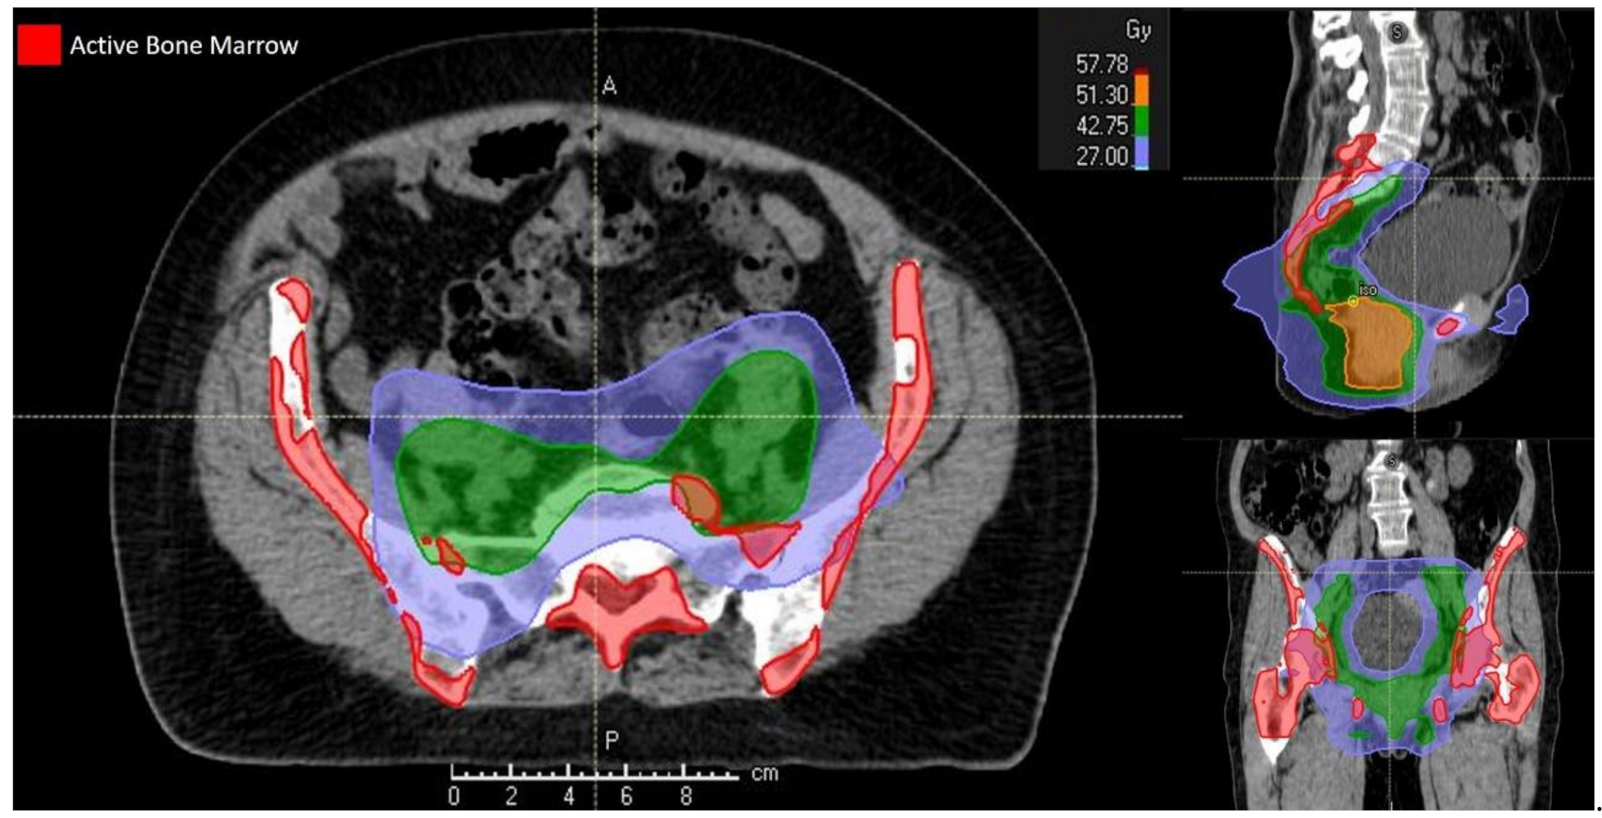

The planning strategy used, typically based on a pre-defined wishlist of clinical objectives and priorities, was integrated by the use of global parameters such as priorities between targets and organs at risk, dose fall-off, maximum dose and cold spot management. The standard organs at risk considered in the optimization process were bladder, external genitalia, large and small bowel and femoral heads in accordance with Kachnich et al. [4,16]. Dose constraints for active pelvic BM were targeted to both PBM and LSBM, as previously reported [9,18,19]. Table 1 reported the full set of dose constraints employed during the planning process. The treatment was finally delivered using the Elekta Synergy platform. Figure 2 shows the isodose distribution for a BM-sparing IMRT plan delivered to a patient in the present study.

Figure 2. Isodose distribution for a bone marrow-sparing intensity-modulated radiotherapy treatment plan.